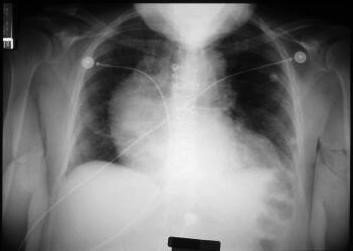

damar img 2  damar img 3

Rentgenoqrafiyada mediastinumun genişlənməsi

Aortoqrafiyada qalxan aorta anevrizması